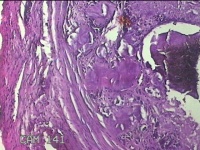

左外踝包块

性别

男

年龄

31岁

临床诊断

皮下结节

一般病史

发现左外踝包块1年余。

标本名称

大体所见

灰白暗红色包块1.8x1.3x0.7cm一个,表面糜烂,切开包块,内见大量石灰样物,内壁粗糙。

去了解病史,应该是痛风结节。